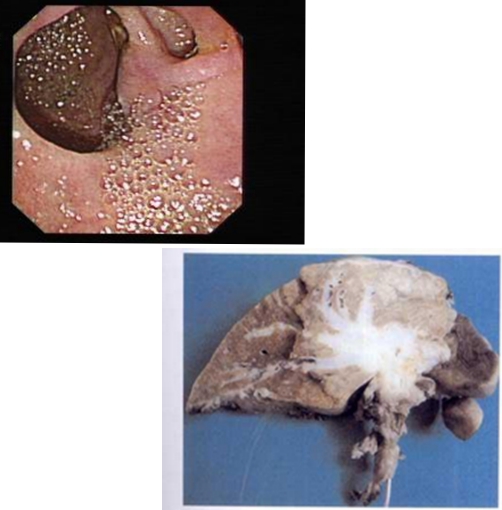

下段膽管癌

小細胞膽管癌

早期肝膽管癌

內膽管癌早期症狀